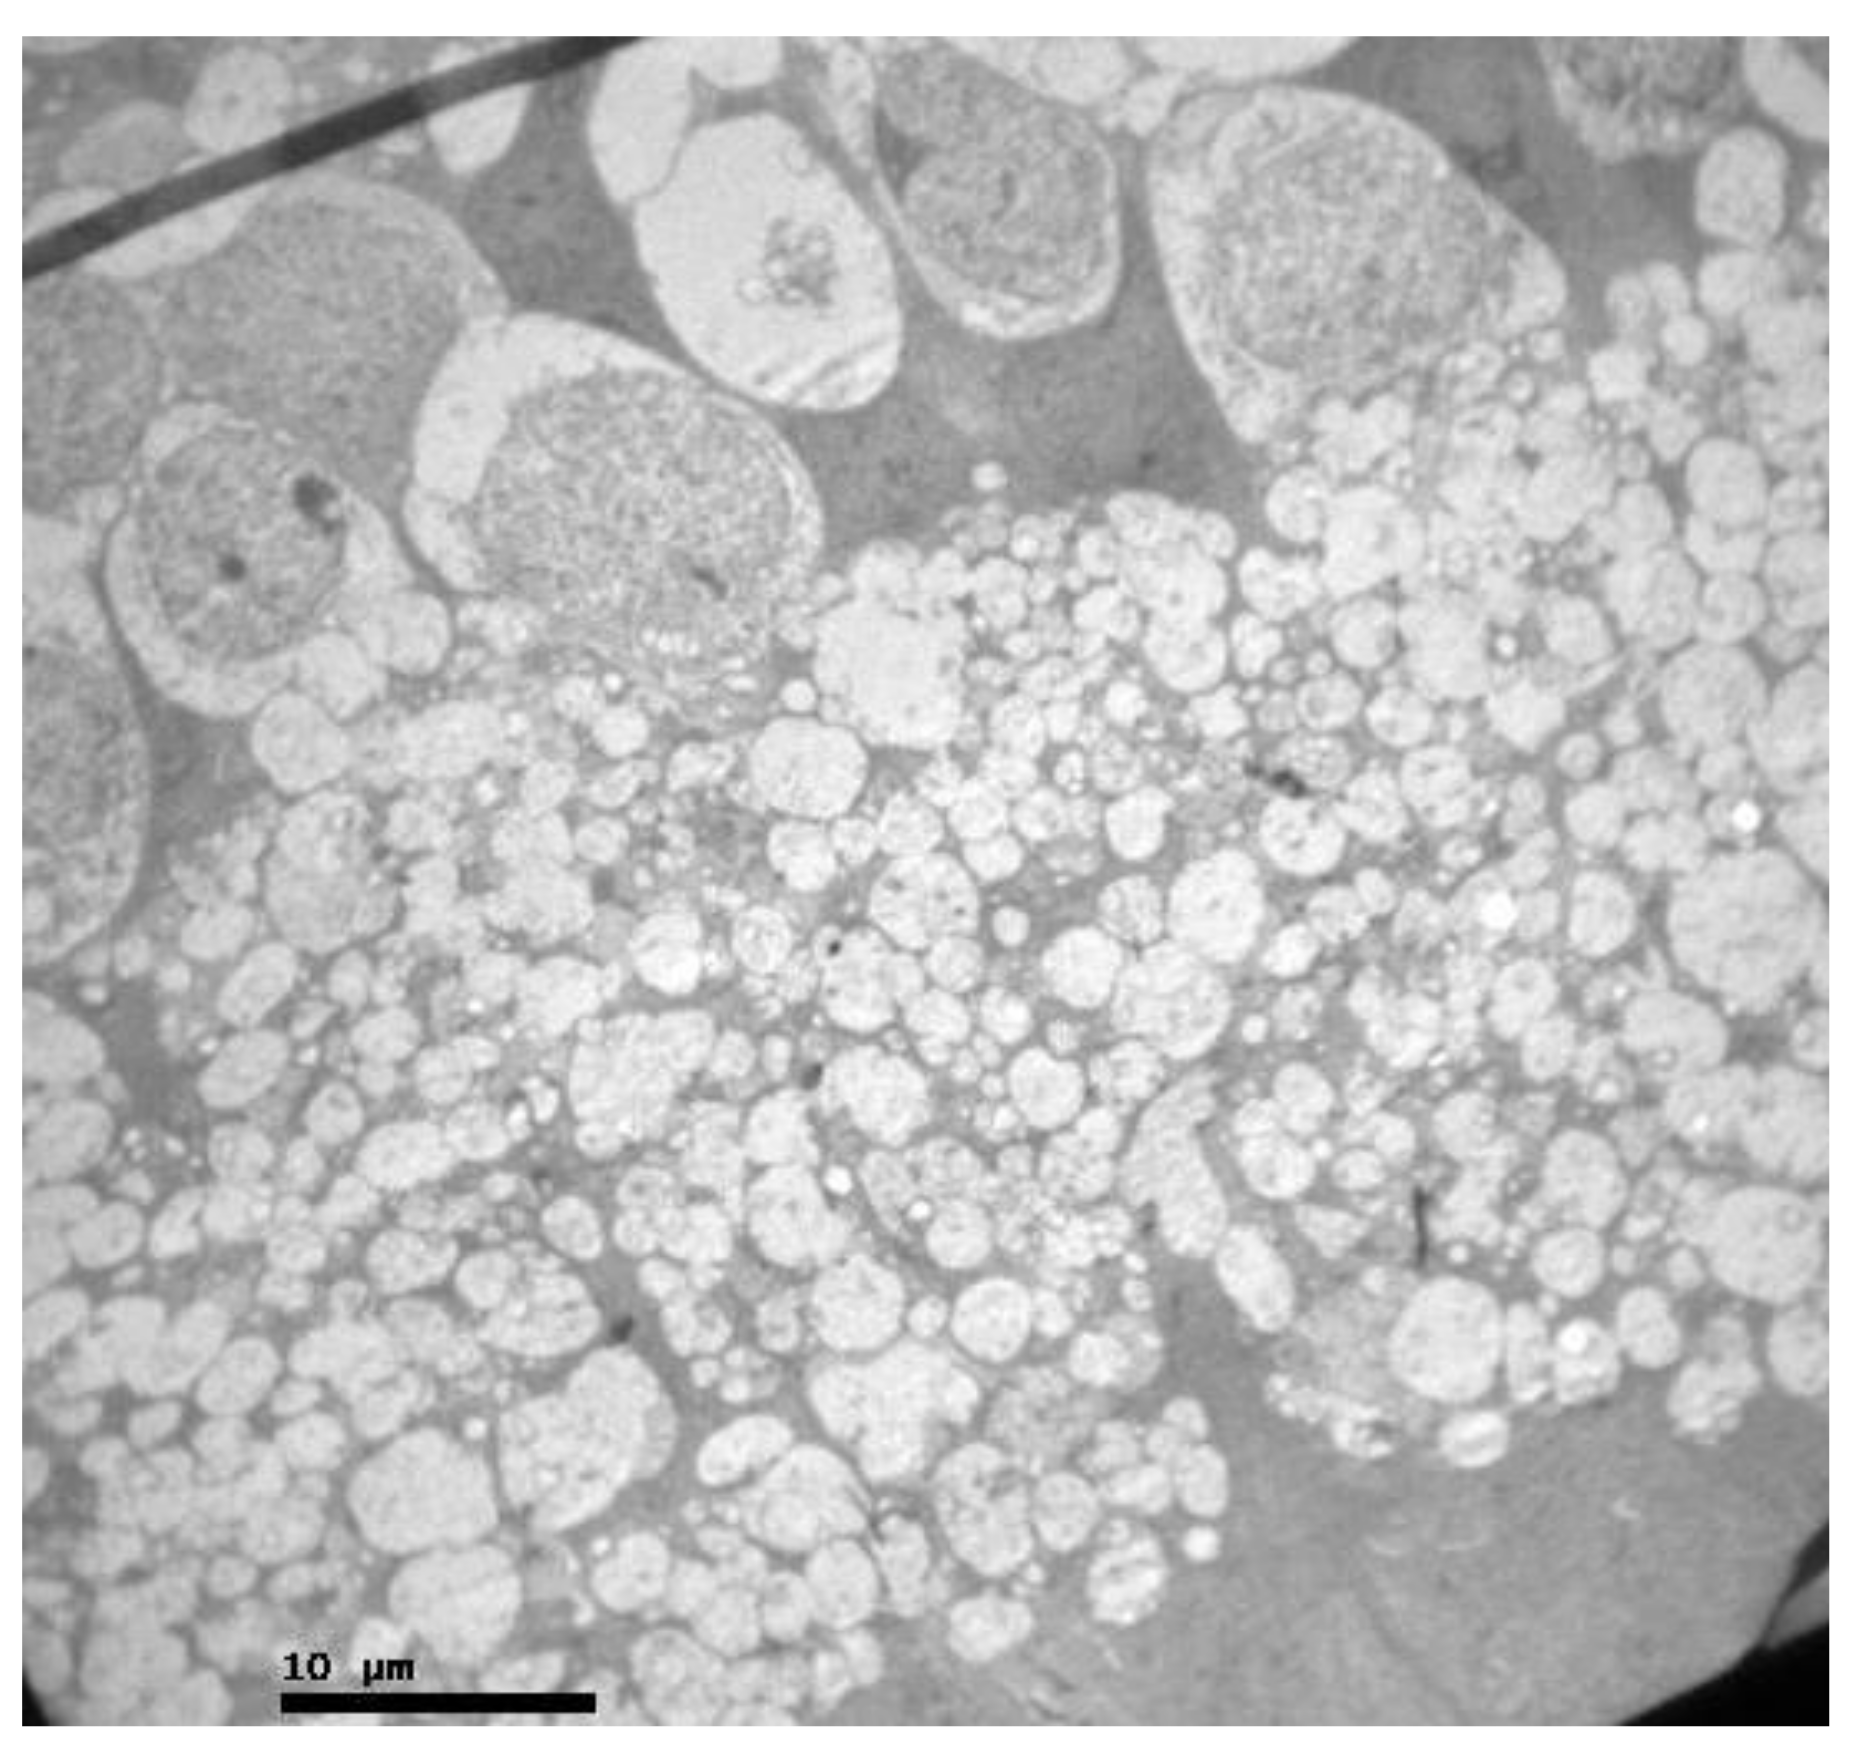

2.1. Group C

2.2. Group V

2.3. Group M